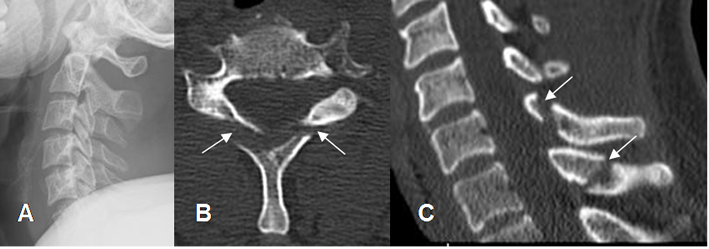

Fig 206 A. Luxación de facetas.

A: TAC reconstrucción sagital. Anterolistesis post-traumática.

B: TAC axial y C: TAC reconstrucción sagital. Luxación de las articulaciones interapofisiarias, con desplazamiento anterior de las facetas superiores. (Flecha delgada). Facetas normales en el segmento inferior. (Flecha gruesa).

Fig 206 B. Luxación de facetas.

A: RM sagital en T2. Igual paciente anterior. Anterolistesis post-traumática, con sección medular. (Flecha delgada).

Presencia de colección prevertebral. (Flecha gruesa).

B: RM sagital en T2. Luxación de las articulaciones interapofisiarias, con desplazamiento anterior de las facetas superiores. Facetas normales en el segmento inferior. (Flecha gruesa).